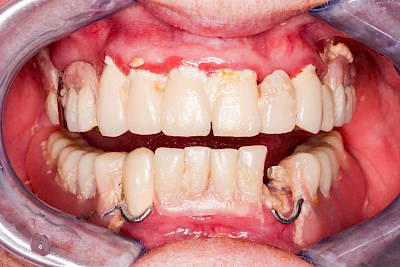

Ist zunächst nur das Zahnfleisch von der Entzündung betroffen, spricht man von Gingivitis. Später, wenn auch der Knochen um die Zähne herum entzündet ist, spricht man von einer Parodontitis. Bei der Parodontitis wird der Knochen nach und nach abgebaut und das Zahnfleisch zieht sich zurück. Die Zahnhälse und Zahnwurzeloberflächen liegen mehr und mehr frei. Die Zähne werden zunehmend lockerer und fallen schließlich aus.

Gingivitis & Parodontitis: Stadien